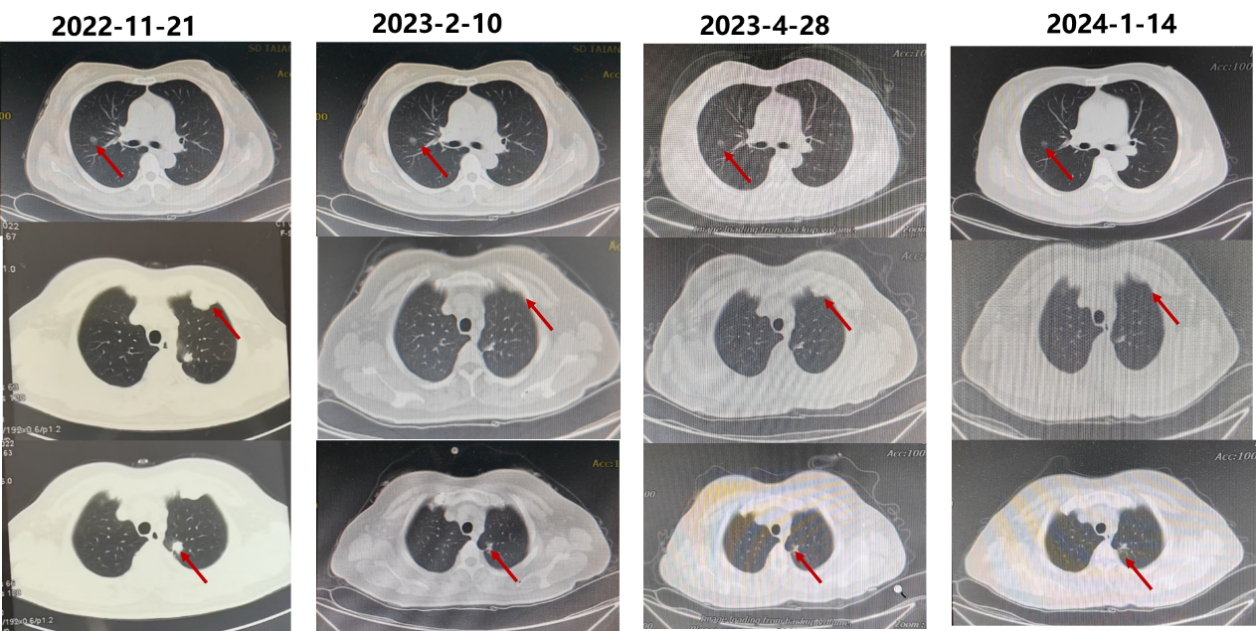

2022年11月21日-2024年4月23日,予“阿来替尼 600mg bid”单药口服治疗。治疗后,患者胸骨后疼痛、咳嗽、咳痰、憋喘等症状逐渐减轻至消失。胸部CT(2023-02-10至2024-01-14,图2):左肺癌治疗后,左肺上叶见条片影,边界不清,未见明确肿块; 双肺小结节灶大者约9mm左右; 纵隔脂肪间隙清晰,未见明显肿大淋巴结。双侧胸腔未见积液。

2023-09-01复查PET-CT(图3):1.左肺癌治疗后,左肺上叶尖后段少许条片状密度增高影,邻近胸膜粘连,右肺上叶后段见一磨玻璃密度结节,均较前相仿,FDG 摄取无增高。2.双颈部、锁骨上、纵隔、腹腔、腹膜后、盆腔、腹股沟未见明显肿大淋巴结。3.扫及胸骨、多发胸腰骶椎椎体、双侧髂骨、坐骨及右侧股骨见多发小结节状高密度影,FDG摄取无增高。4.心包及双侧胸腔无积液。

疗效评估:PR。

2024年4月29日复查CT(图4):左肺上叶少许条片影、右肺上叶结节均较前相仿;右肺上叶后段磨玻璃密度影较前略增大,双肺另见多个微小结节、类结节,较前略增大;枕骨斜坡、胸腰椎、双侧部分肋骨、双侧肩胛骨、右肱骨头、双侧锁骨及胸骨见多发高密度影,较前范围增大。

疗效评估:PD。

PFS1=18个月。